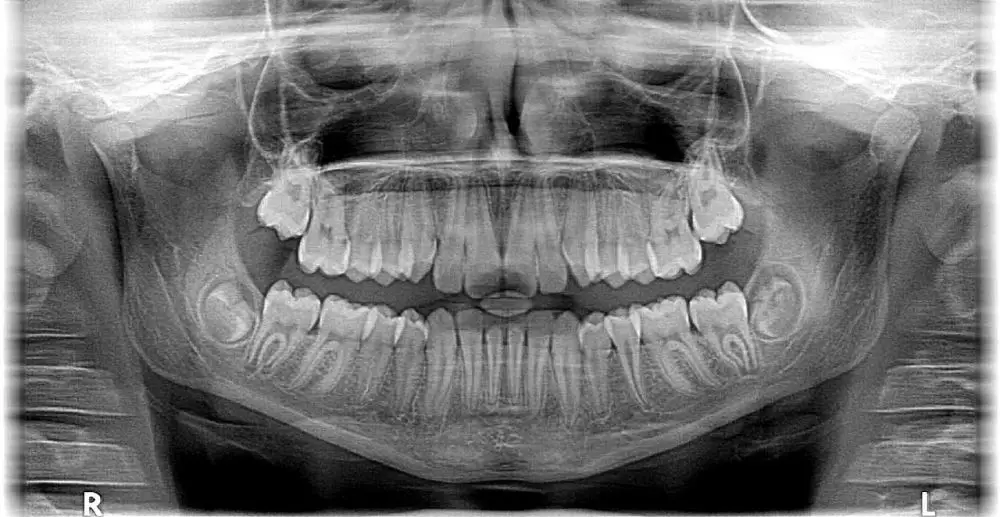

Brilio.net - Gigi bungsu, yang dikenal juga sebagai gigi geraham ketiga, biasanya muncul pada usia antara 17 hingga 25 tahun. Meskipun sebagian orang tidak mengalami masalah serius, bagi sebagian lainnya, kemunculan gigi bungsu bisa menjadi sumber ketidaknyamanan dan bahkan menimbulkan komplikasi serius.

Pada dasarnya, gigi bungsu adalah sisa evolusi dari nenek moyang kita yang membutuhkan tambahan gigi geraham untuk mengunyah makanan keras dan mentah. Namun, dengan perubahan pola makan manusia modern dan evolusi struktur rahang, ruang untuk gigi bungsu menjadi semakin sempit. Akibatnya, gigi bungsu sering kali tumbuh miring, terjebak di dalam gusi, atau menekan gigi lain sehingga menyebabkan rasa sakit dan peradangan.

2. Ruang mulut tidak mencukupi

Ketika gigi bungsu tumbuh tetapi tidak memiliki ruang yang cukup di dalam mulut, hal ini dapat menyebabkan berbagai masalah seperti impaksi, di mana gigi bungsu terjebak di bawah gusi atau hanya sebagian keluar. Impaksi ini bisa menimbulkan rasa sakit, pembengkakan, serta struktur rahang yang bermasalah.